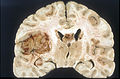

Macroscopy

Features:

- Usu. in white matter.

- central necrotic core.

- ill-defined borders.

- yellowish to dark-brown changes.

- midline shift due to tumor mass.

- In the corpus callosum as bihemispheric "butterfly glioma"